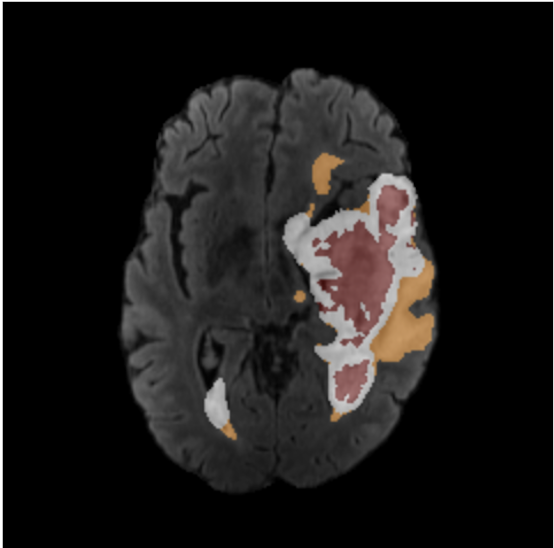

BraTS Quality Control

Interactive tool for reviewing and labeling BraTS brain MRI images with tumor segmentation overlays.